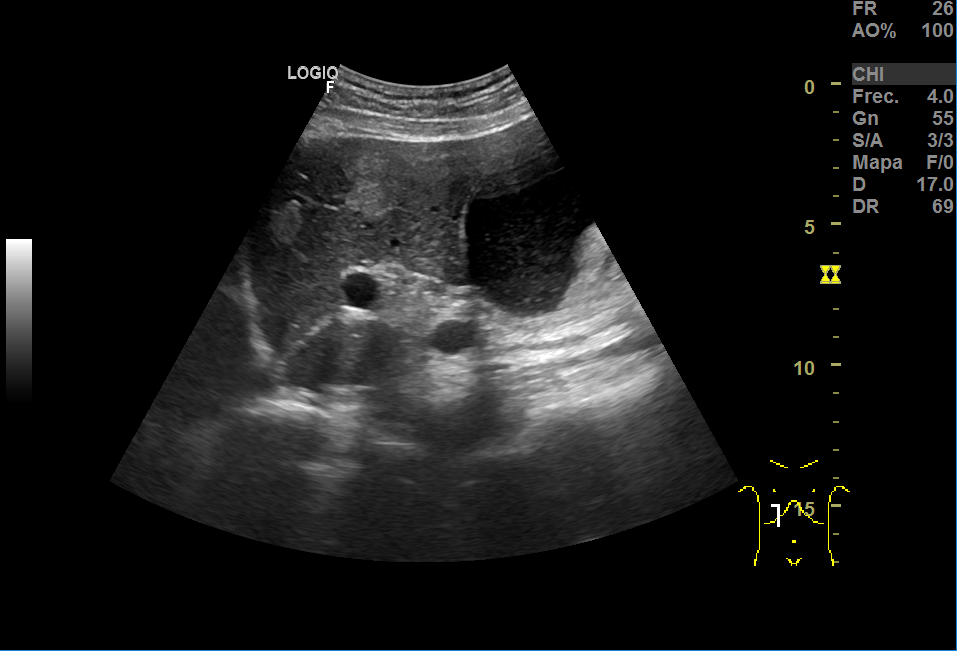

En la ecografía, a nivel hepático, vimos unas imágenes hiperecoicas redondeadas hipervascularizadas: una de aproximadamente 5 cm de diámetro y otra de 3cm, sospechosas de LOEs (lesiones ocupantes de espacio).

Repite la ecografia: En el segmento IV, aparece una imagen redondeada de 30x40 mm heterogénea, iso-hipoecogénica sin captación ecodoppler que podría ser un angioma, HFN (hiperplasia nodular focal) u otra posibilidad; otra imagen oval hiperecogénica de 19 mm, que sugiere angioma como primera posibilidad.

El aspecto de los hemangiomas hepáticos en la ecografía son lesiones de pequeño tamaño (inferior a 30 mm), hiperecoicas, bien delimitadas, homogéneas, con refuerzo acústico posterior y sin captación en el estudio Doppler. En cambio, el aspecto ecográfico atípico como el de nuestro caso: mayor tamaño, heteroecoico con zona central hipoecoica y límites irregulares o mal definidos, requiere de otras técnicas.